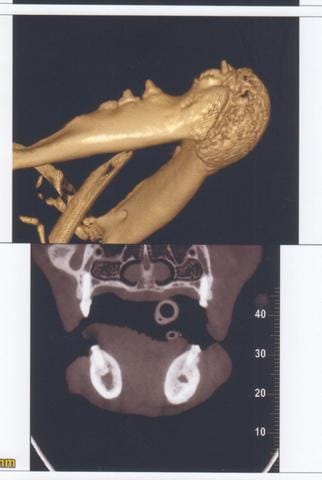

Cône Beam New Tom 5G

Technique : Examen des mâchoires en section axiale ; images natives de 0,1mm ; reconstruction MPR et 3D 0,1mm temps d’exposition total : 7.3s ; mAs : 23.08 ; kV 110kV ; CDTi/V (dose délivrée / surface exposée) : 3.27 mGy

Description

Mise en évidence d’une masse homogène se développant dans la base du menton avec néoformation osseuse de type proliférative.

Centre de la lésion au niveau de l’alvéole de la canine gauche absente et extension hauteur de PM3 pour la mandibule gauche et Pm2 pour la mandibule droite.

Limite carcinologique appréciée (5mm) en mésial des carnassières.